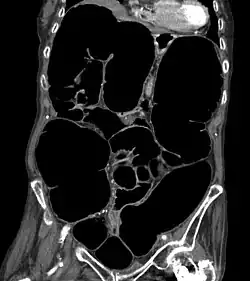

Coronale Rekonstruktion eines CT-Scans des Abdomens einer älteren Frau mit einem Ogilvie-Syndrom (Pseudoobstruktion des Dickdarmes)

Die Diagnostik der Erkrankung ist einfach, da das Röntgenbild sehr charakteristische Zeichen aufweist. Der gesamte Dickdarm ist breit mit Luft gefüllt, vor allem der aufsteigende Teil des Dickdarmes erreicht eine Breite von oft mehr als 10 cm.